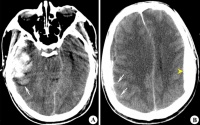

右额颞叶脑挫裂伤合并蛛网膜出血

伤中,首次CT的阳性发现率竟占18%,并有5%需行手术治疗,强调早期CT检查的必要性。

CT扫描[编辑 | 编辑源代码]

对脑挫裂伤与脑震荡可以作出明确的鉴别诊断,并能清楚地显示脑挫裂伤的部位、程度和有无继发损害,如出血和水肿情况。同时,可根据脑室和脑池的大小、形态和移位的情况间接估计颅内压的高低。尤为重要的是,对一些不典型的病例,可以通过定期CT扫描,动态地观察脑水肿的演变或迟发性血肿的发生。近年来,在有此设备的医院CT已作为急性头伤的常规检查,因为单靠伤史和查体难以作出超早期诊断。Stein等(1990)指出在GCS13~15危害较小的轻型头